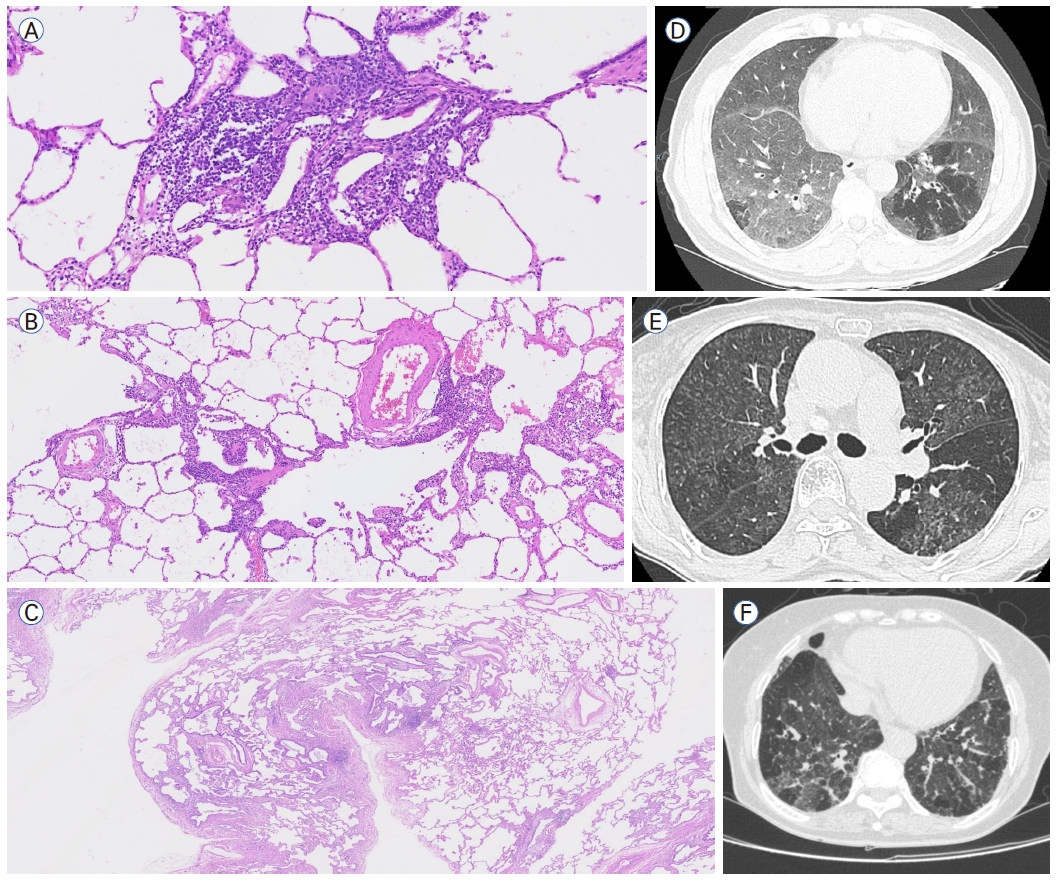

| Morphologic patterns by pathology and imaging |

Radiological-histological patterns |